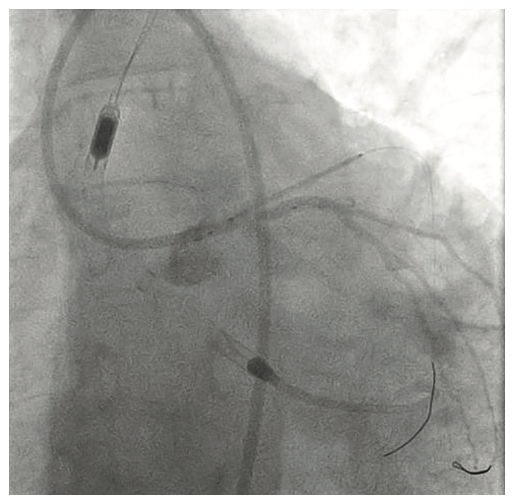

Following the Perclose placement, we upsized to a 14 Fr x 13 cm Cook Medical sheath (Figures 7-8), and through that, advanced a JR catheter into the ventricle and switched out for the Impella 2.5 device (Figure 9). A JR4 and eventually, an Amplatz right (AR) mod, was used from the right ulnar to engage the RCA, and an Extra Backup (EBU) 3.5, 7 Fr (Medtronic) was used from the groin. Dual angiography was performed (Figure 10). Once the activated clotting time (ACT) was >300 seconds, the ramus was wired with a Marvel wire (Boston Scientific). We attempted to cross the LAD CTO using a Corsair (Asahi Intecc) and a Pilot 200 (Abbott Vascular). The Pilot 200 crossed, but it appeared to be in the diagonal and could not be redirected down the LAD. A Gaia second (Asahi Intecc) was able to cross into the LAD (Figure 11), and at that point, was switched out via the Corsair for a workhorse wire, a Runthrough (Terumo). An 0.9 laser (Spectranetics) was used perform laser atherectomy for a minute and a half on the LAD (Figure 12), but we could not get the catheter across. However, this allowed us to advance a balloon across the lesion and we predilated with a 1.5 mm x 20 mm Mini Trek (Abbott Vascular) and then a 2.0 mm x 20 mm balloon. The same 2.0 mm x 20 mm balloon was used in the ramus. A 2.5 mm x 15 mm AngioSculpt (Philips) was used to predilate the LAD, but on its return, the AngioSculpt became stuck and would not come back. We got it partially into the guide and then the shaft broke. We had part of the catheter in the guide and part of it in the coronary (the left main). We initiated a series of procedures to remove the AngioSculpt, first attempting use of a GuideLiner (Vascular Solutions) to envelope the balloon, but this was unsuccessful (Figure 13). The GuideLiner kept pushing the device further out. We tried trapping it; that was also unsuccessful. We were able to get a Mini Trek balloon distal, thinking it could be inflated and pulled back; that did not work. We then put the 4 wires down, wrapped the wires around and pulled back, getting it partially in the guide, but we could not get it all the way in. We got a Mini Trek down, used the GuideLiner to put a 2.0 down, and attempted an anchor technique that did not work, but this time, when we pulled the Mini Trek 2.0 back, it dislodged the balloon. The AngioSculpt was able to come in the guide and was removed without losing wire position. We rewired the ramus, performed dilation of the LAD and ramus with a 2.5 mm noncompliant balloon, and performed intravascular ultrasound (IVUS). The LAD was about 2.75 mm2 distally and the ramus was 3.0 mm2, with the left main being approximately 3.75 mm2. A double kissing (DK) crush technique was used with a 2.75 mm x 38 mm Synergy stent (Boston Scientific) to the LAD and 3.0 mm x 24 mm Synergy to the ramus; then we used proximal optimization technique (POT) with a 3.75 mm NC balloon (Medtronic) and a final kiss with 3.0 mm x 20 mm NC balloons (Figures 14-17). IVUS was used to confirm that the stents were well apposed. The Impella device was weaned and removed, keeping the sheath in. From the groin sheath, a balloon was advanced into the left subclavian and we did a dry close. We inflated an 8.0 mm x 40 mm balloon at 3 atmospheres (nominal is 6 atmospheres) (Figure 18). Once the pressure tracing from the axillary sheath side arm dropped, we were able to remove the sheath and then completed the Perclose. There was some slight track ooze (Figure 19). Therefore, we performed two 5-minute inflations with the 8.0 mm x 40 mm balloon at 3 atmospheres (nominal is 6 atmospheres), and there was complete resolution of the track ooze. No extravasation was noted (Figures 20-21). The ulnar sheath was sutured in, we made sure there were no issues overnight, and the patient was discharged the following morning.

- A pigtail catheter is then used to access the aortic valve to the left ventricle.

- An .018-inch Impella wire (with a curve at the tip) is then advanced through the pigtail catheter.

- Impella CP device is then inserted over the stiff wire and advanced under fluoroscopic guidance into the left ventricle.